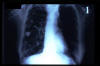

TBC pulmonar antigua